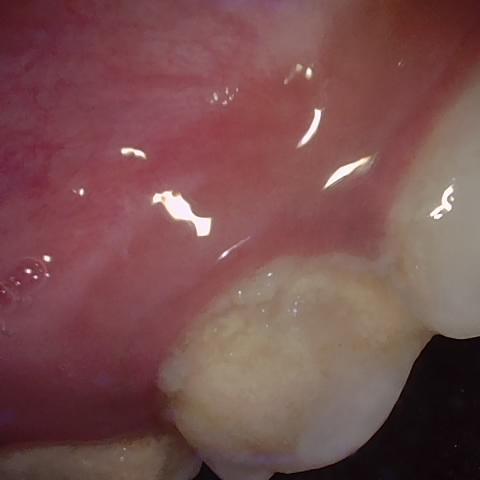

Annotated as "Good"